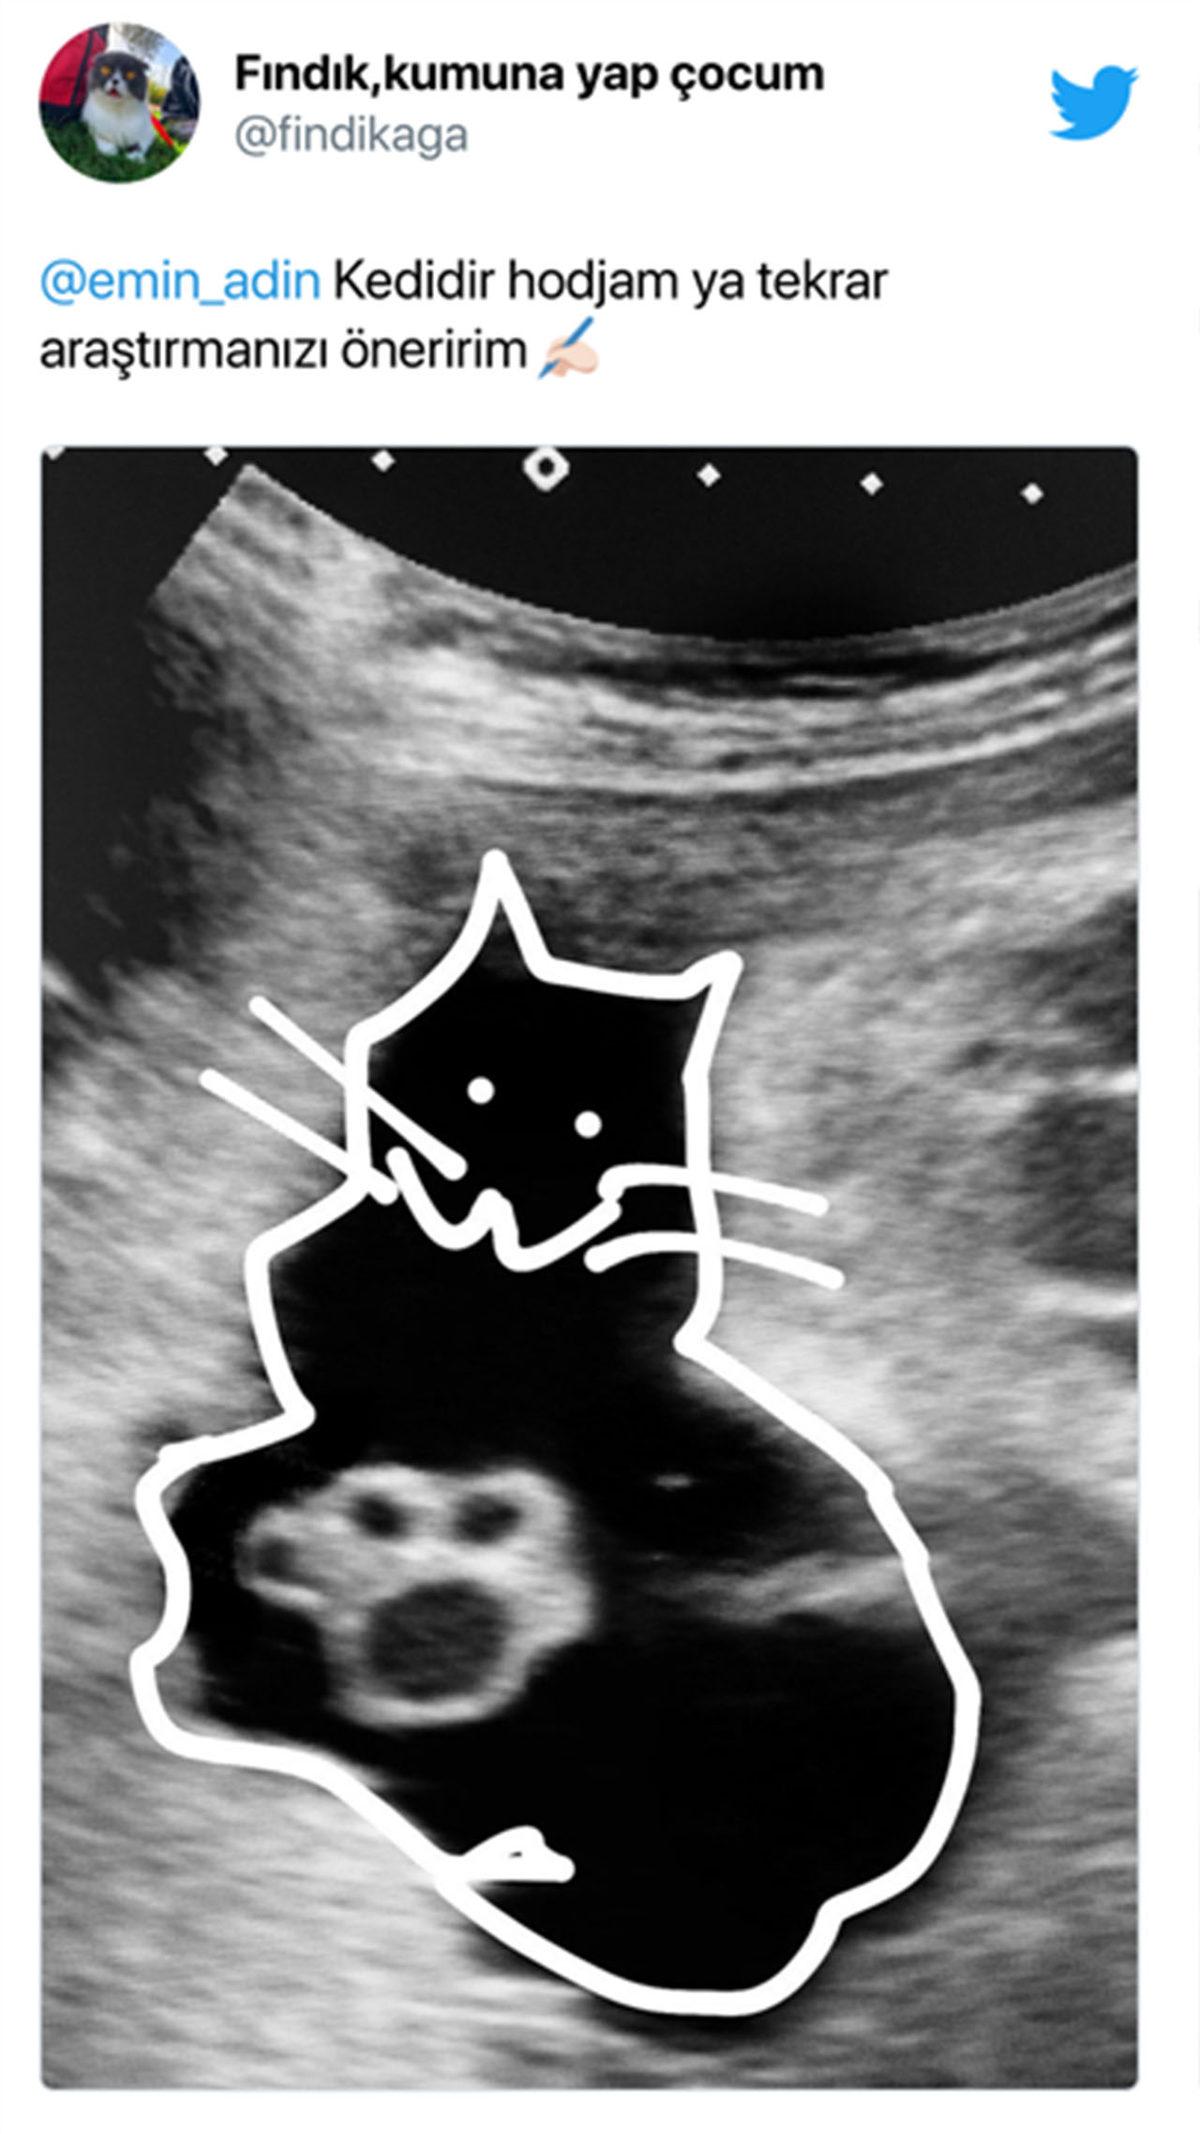

Geçtiğimiz günlerde bir doktor, Twitter'da hastasının ultrason görüntüsünü paylaştı. İlk bakışta patiye ve hatta muştaya benzetilebilecek bu görüntü, hastasının da kafasını karıştırmış olmalı ki "Doktor Bey bu patiler ne, kedi mi doğuracağım?" diye sordu.

Doktorun paylaştığı tweet'in altında şöyle komikli yorumlar da bulunuyor: